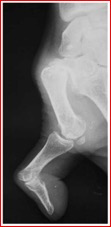

La rhizarthrose est très fréquente et de plus en plus mal tolérée surtout pendant les poussées inflammatoires douloureuses. Même si cette douleur reste localisée à la base du pouce, elle rend difficile les gestes de la vie quotidienne comme serrer une clé, ouvrir un bocal ou peler un fruit… ces douleurs peuvent devenir permanente, responsable de raideur et de gonflement. Par la suite vont apparaître des déformations avec des subluxations de la base du 1er métacarpien avec des retentissements sur la 1ère commissure en la refermant et une exploitation exagérée de la MP provoquant son extension pour aboutir à la déformation caricaturale du pouce en Z de chiffre (photo)

début de la déformation: hyperextension de la métacarpo-phalangienne pour compenser la fermeture de la 1ère commissure, permettant ainsi de continuer à savoir prendre des gros objets

sans traitement, la rhizarthrose aboutit à cette déformation caricaturale en forme de Z de chiffre